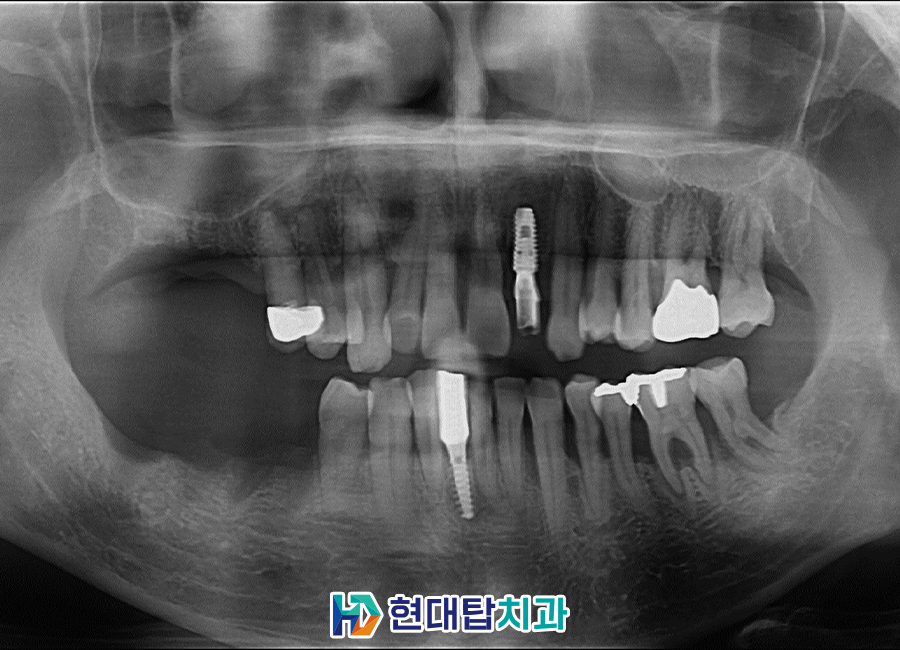

울산동구임플란트 잘하는곳 TOP치과에서는

임플란트를 식립한 후 인공치근과

잇몸뼈가 융합될 수 있도록 충분한

기간을 기다려준 후 보철물의 제작을

진행하고 있습니다.

또한, 왼쪽의 앞니 경우에는

뼈이식을 동반하여 임플란트 식립과

당일 보철치료까지 모두 안정적으로

완료하였습니다.

자연치아와 매우 비슷한 모양과 색깔에

환자분께서는 매우 높은 만족도를

보여주셨습니다.

많은 뼈이식을 동반하여 난이도가

높은 술식임에도 불구하고

큰 불편함 없이 안정적인 진행에

감사 인사를 전해주셨습니다.

다만, 전반적으로 좋지 않았던

잇몸을 완전히 회복하기에는 어려움이

있어 평상시 꾸준한 관리와 주기적인

검진을 당부드렸습니다.